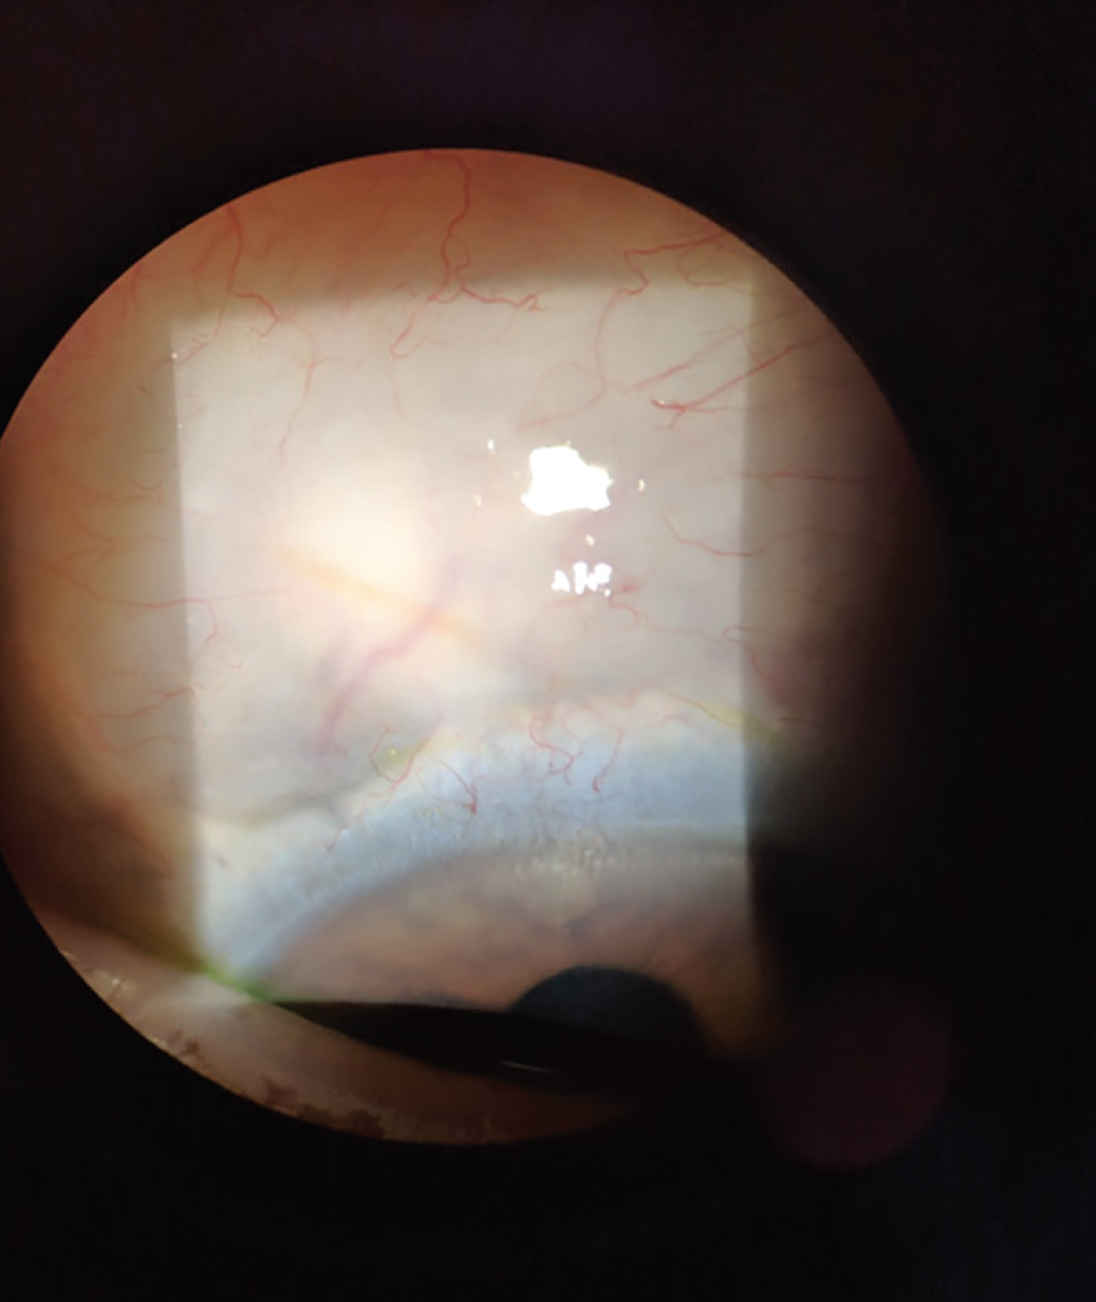

Dr. Sheybani: Figure 5 shows the XEN Gel Stent visible under the conjunctiva postoperatively. This procedure provides significant IOP lowering. The pivotal data show IOP was reduced from a mean of 25.1 mm Hg to 15.9 mm Hg at 12 months and use of hypotensive medications was reduced from a mean of 3.5 to 1.7.7 The speed to visual recovery is excellent. What have your experiences been in terms of IOP outcomes and visual recovery?

Figure 5. The Xen Gel Stent is straight and visible under the conjunctiva postoperatively.

Courtesy of Inder Paul Singh, MD.